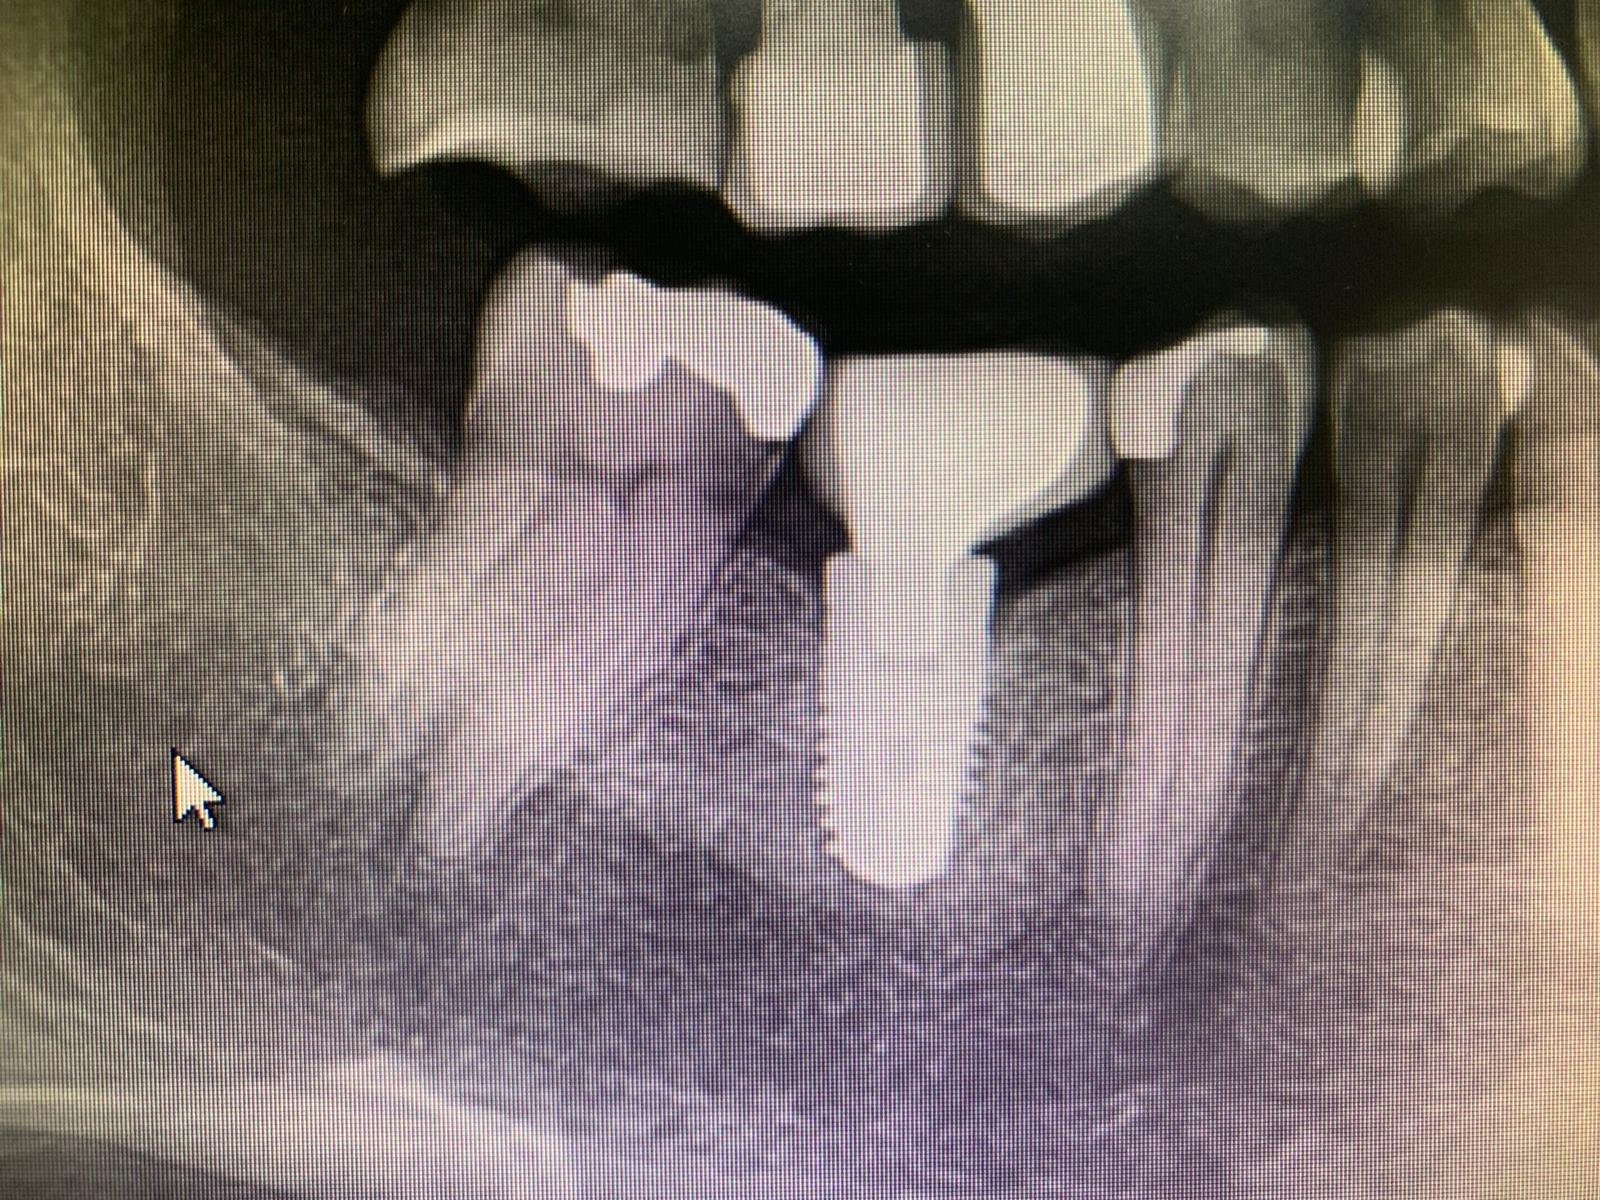

Hola, necesito saber qué implantes lleva mi paciente para cambiar sus coronas, me echáis una mano? Gracias, compañeros!

Buenos días. Paciente acude con puente implanto soportado en la mano. Conexiones de la prótesis en mal estado y solo preservamos 1 tornillo. ( el otro esta fracturado en el [...]

Son dos implantes con conexión hexagonal algo mas estrecha que la conexión de zimmer.